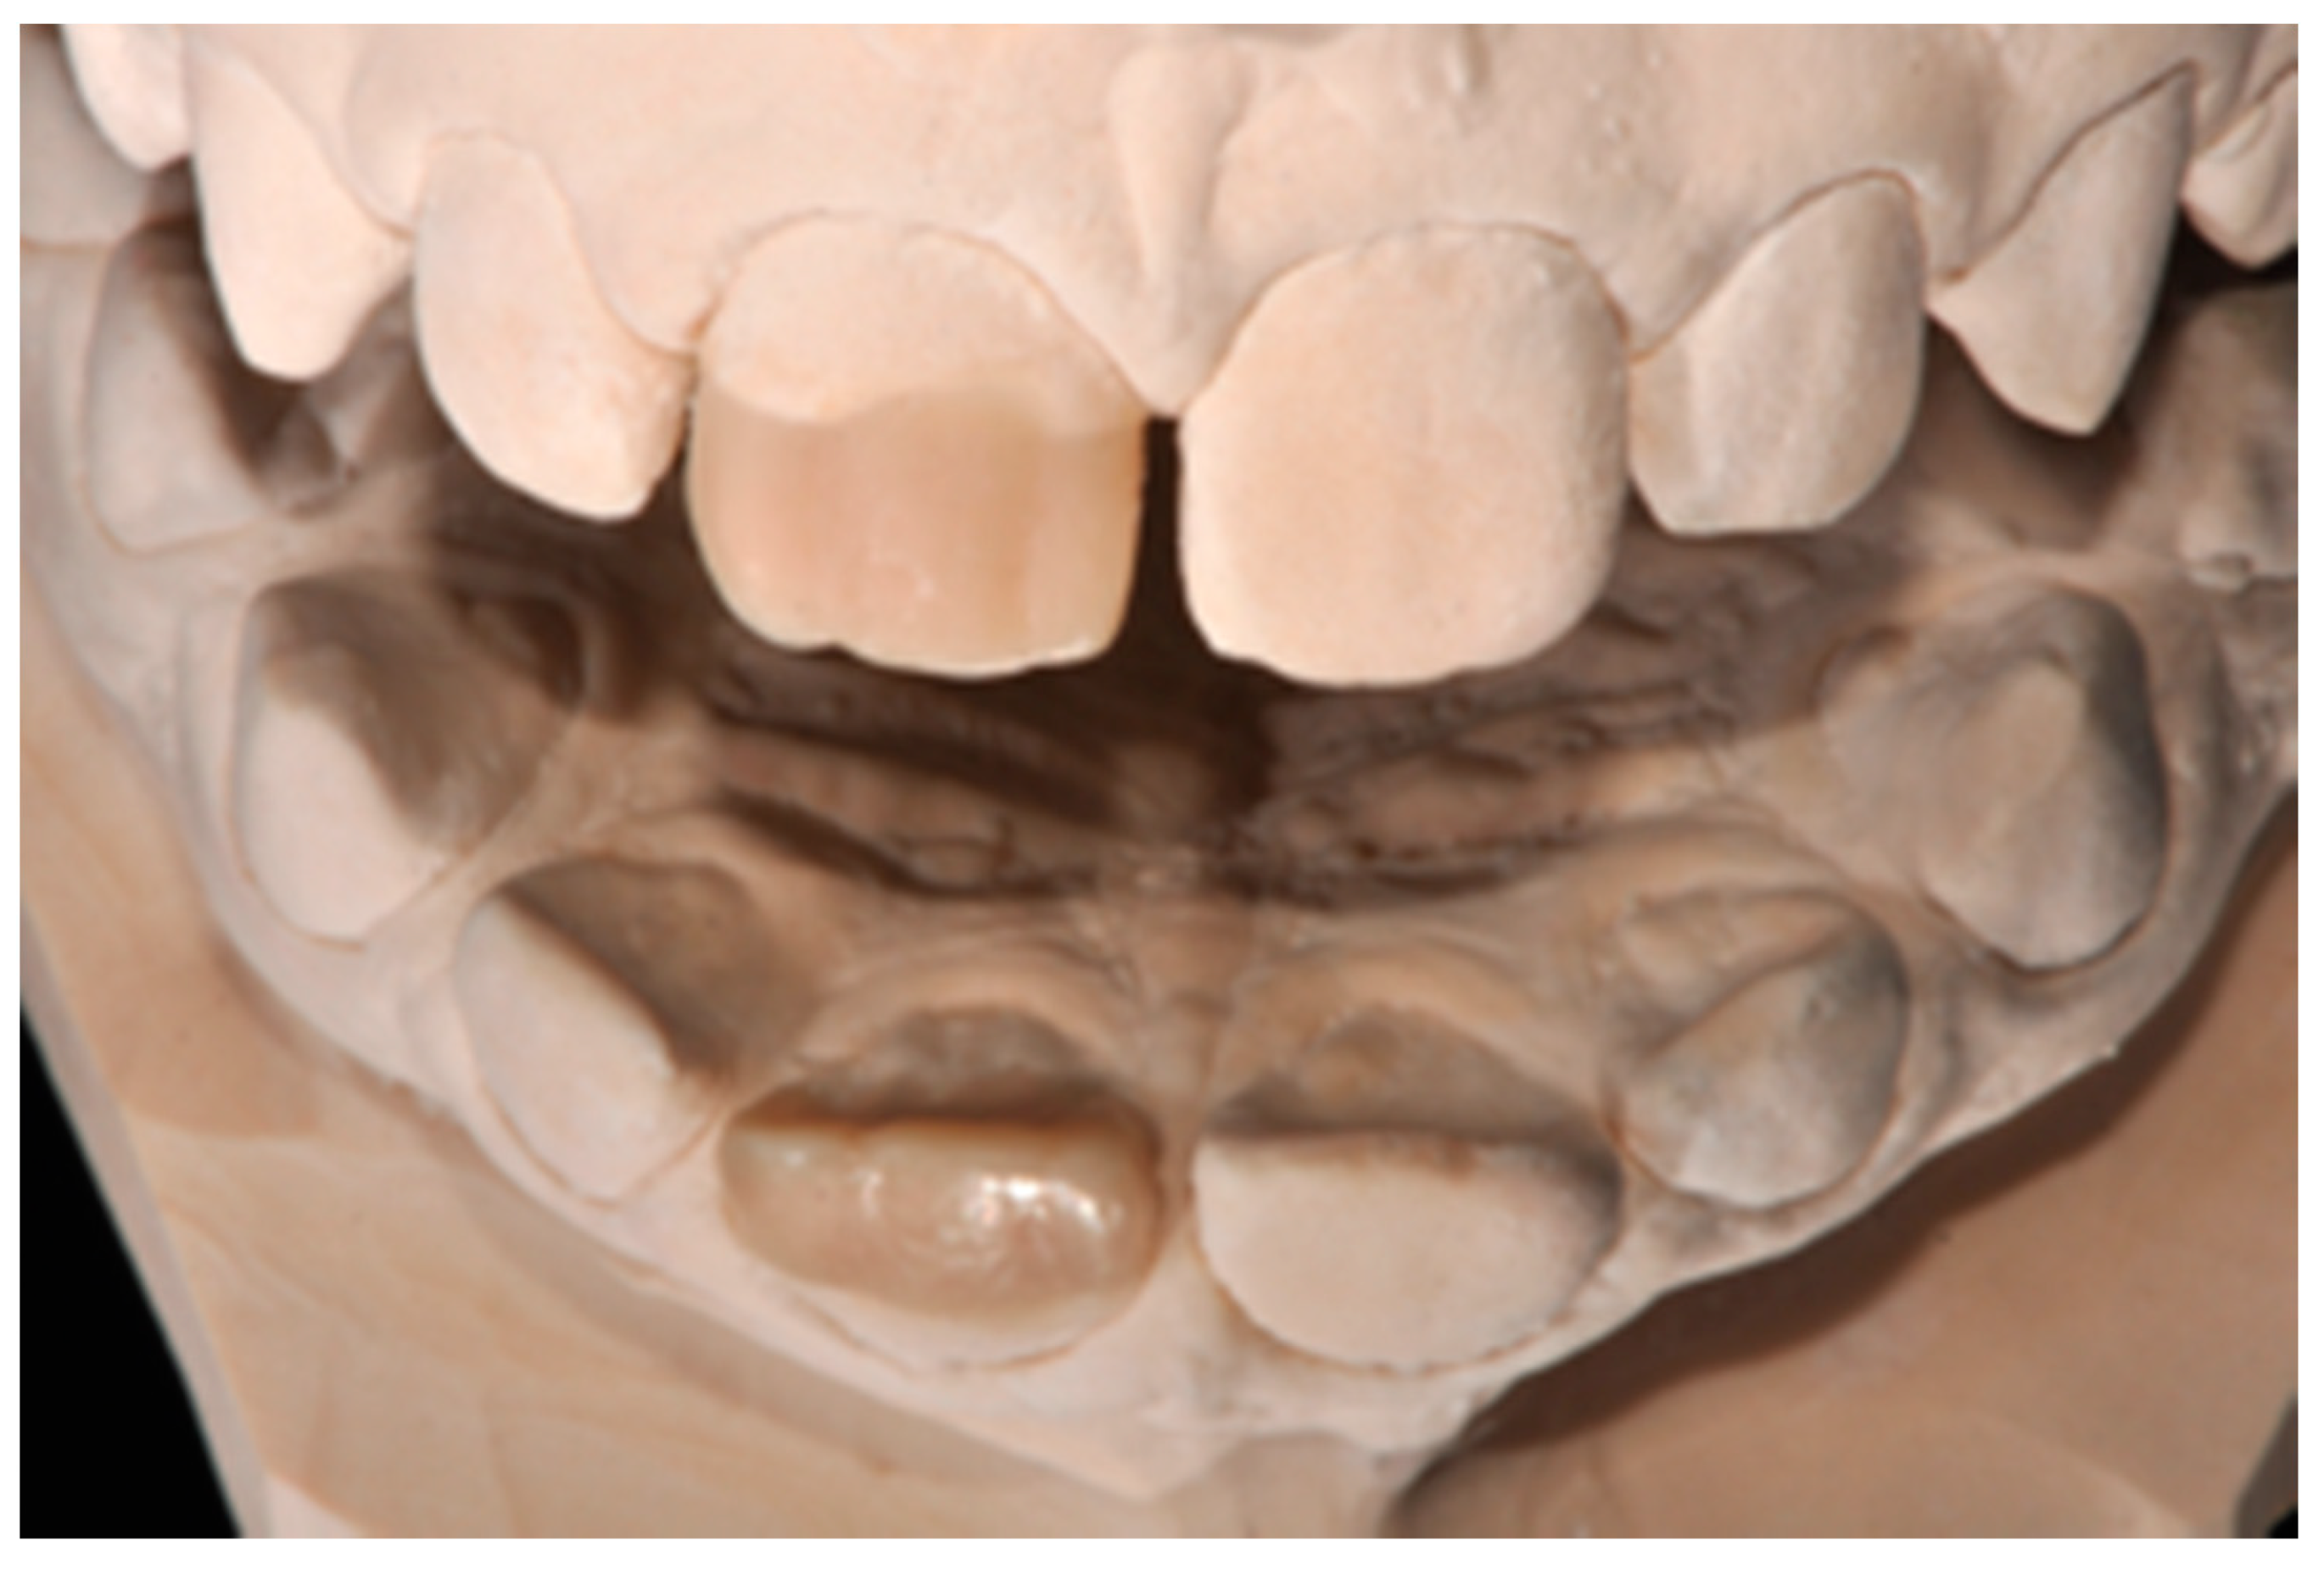

Figure 3.

Wax-up. Reprinted from Restauri diretti nei settori anteriori, G. Paolone, S. Scolavino, © 2021, with permission from Quintessence Publishing Italy.